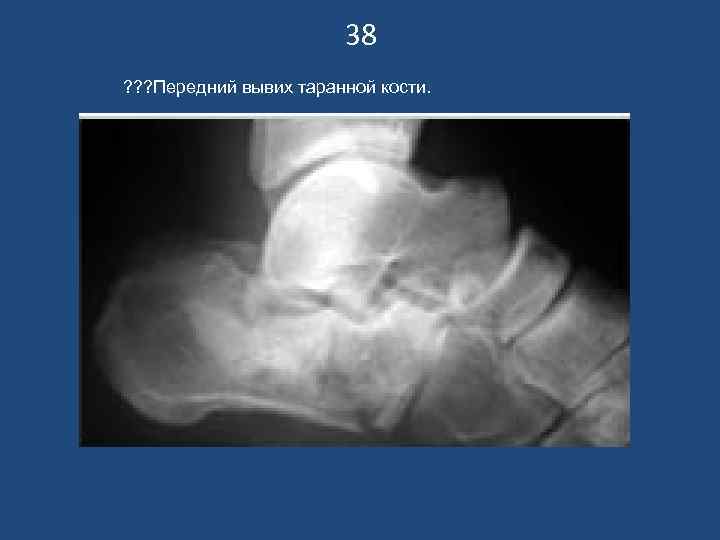

38 ? ? ? Передний вывих таранной кости.

37 Внутрисуставной ? ? ?